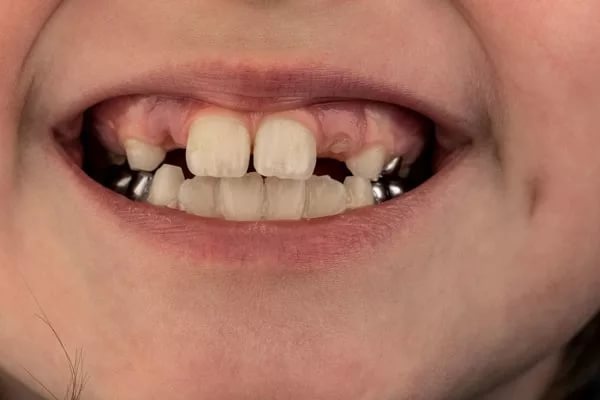

Ви знали про те, що молочні зуби теж можуть мати коронки. Сталеві коронки є одним з найкращих засобів захисту та відновлення молочних зубів. Застосовуються дитячі коронки у маленьких пацієнтів із високою схильністю до розвитку карієсу та при дуже великих каріозних ураженнях.

- техніка Холла - закріплення зуба коронкою без препарування карієсу. Особливо корисна техніка для дітей, які недостатньо співпрацюють, щоб підготувати порожнину механічно. Лікування безболісне, швидке, а результати напрочуд позитивні.

Коронки на молочні моляри виготовлені зі сталі. Вони бувають різних розмірів та підганяються залежно від індивідуальних розмірів зуба.

Установка коронки відбувається швидко, під час процедури дитина відчуває лише тиск. За один-два дні дитина адаптується до нової ситуації в порожнині рота шляхом посиленого прикусу, після чого дискомфорту вже не відзначає.